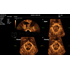

Программное обеспечение для автоматических измерений параметров и оценки функции мышц тазового дна.

Smart Pelvic - новое решение, позволяющее значительно упростить диагностическую процедуру и свести к минимуму время исследования функций мышц тазового дна. Благодаря чрезвычайно простому пользовательскому интерфейсу, программа генерирует стандартную систему координат и автоматически просчитывает все связанные измерения в течение нескольких секунд.